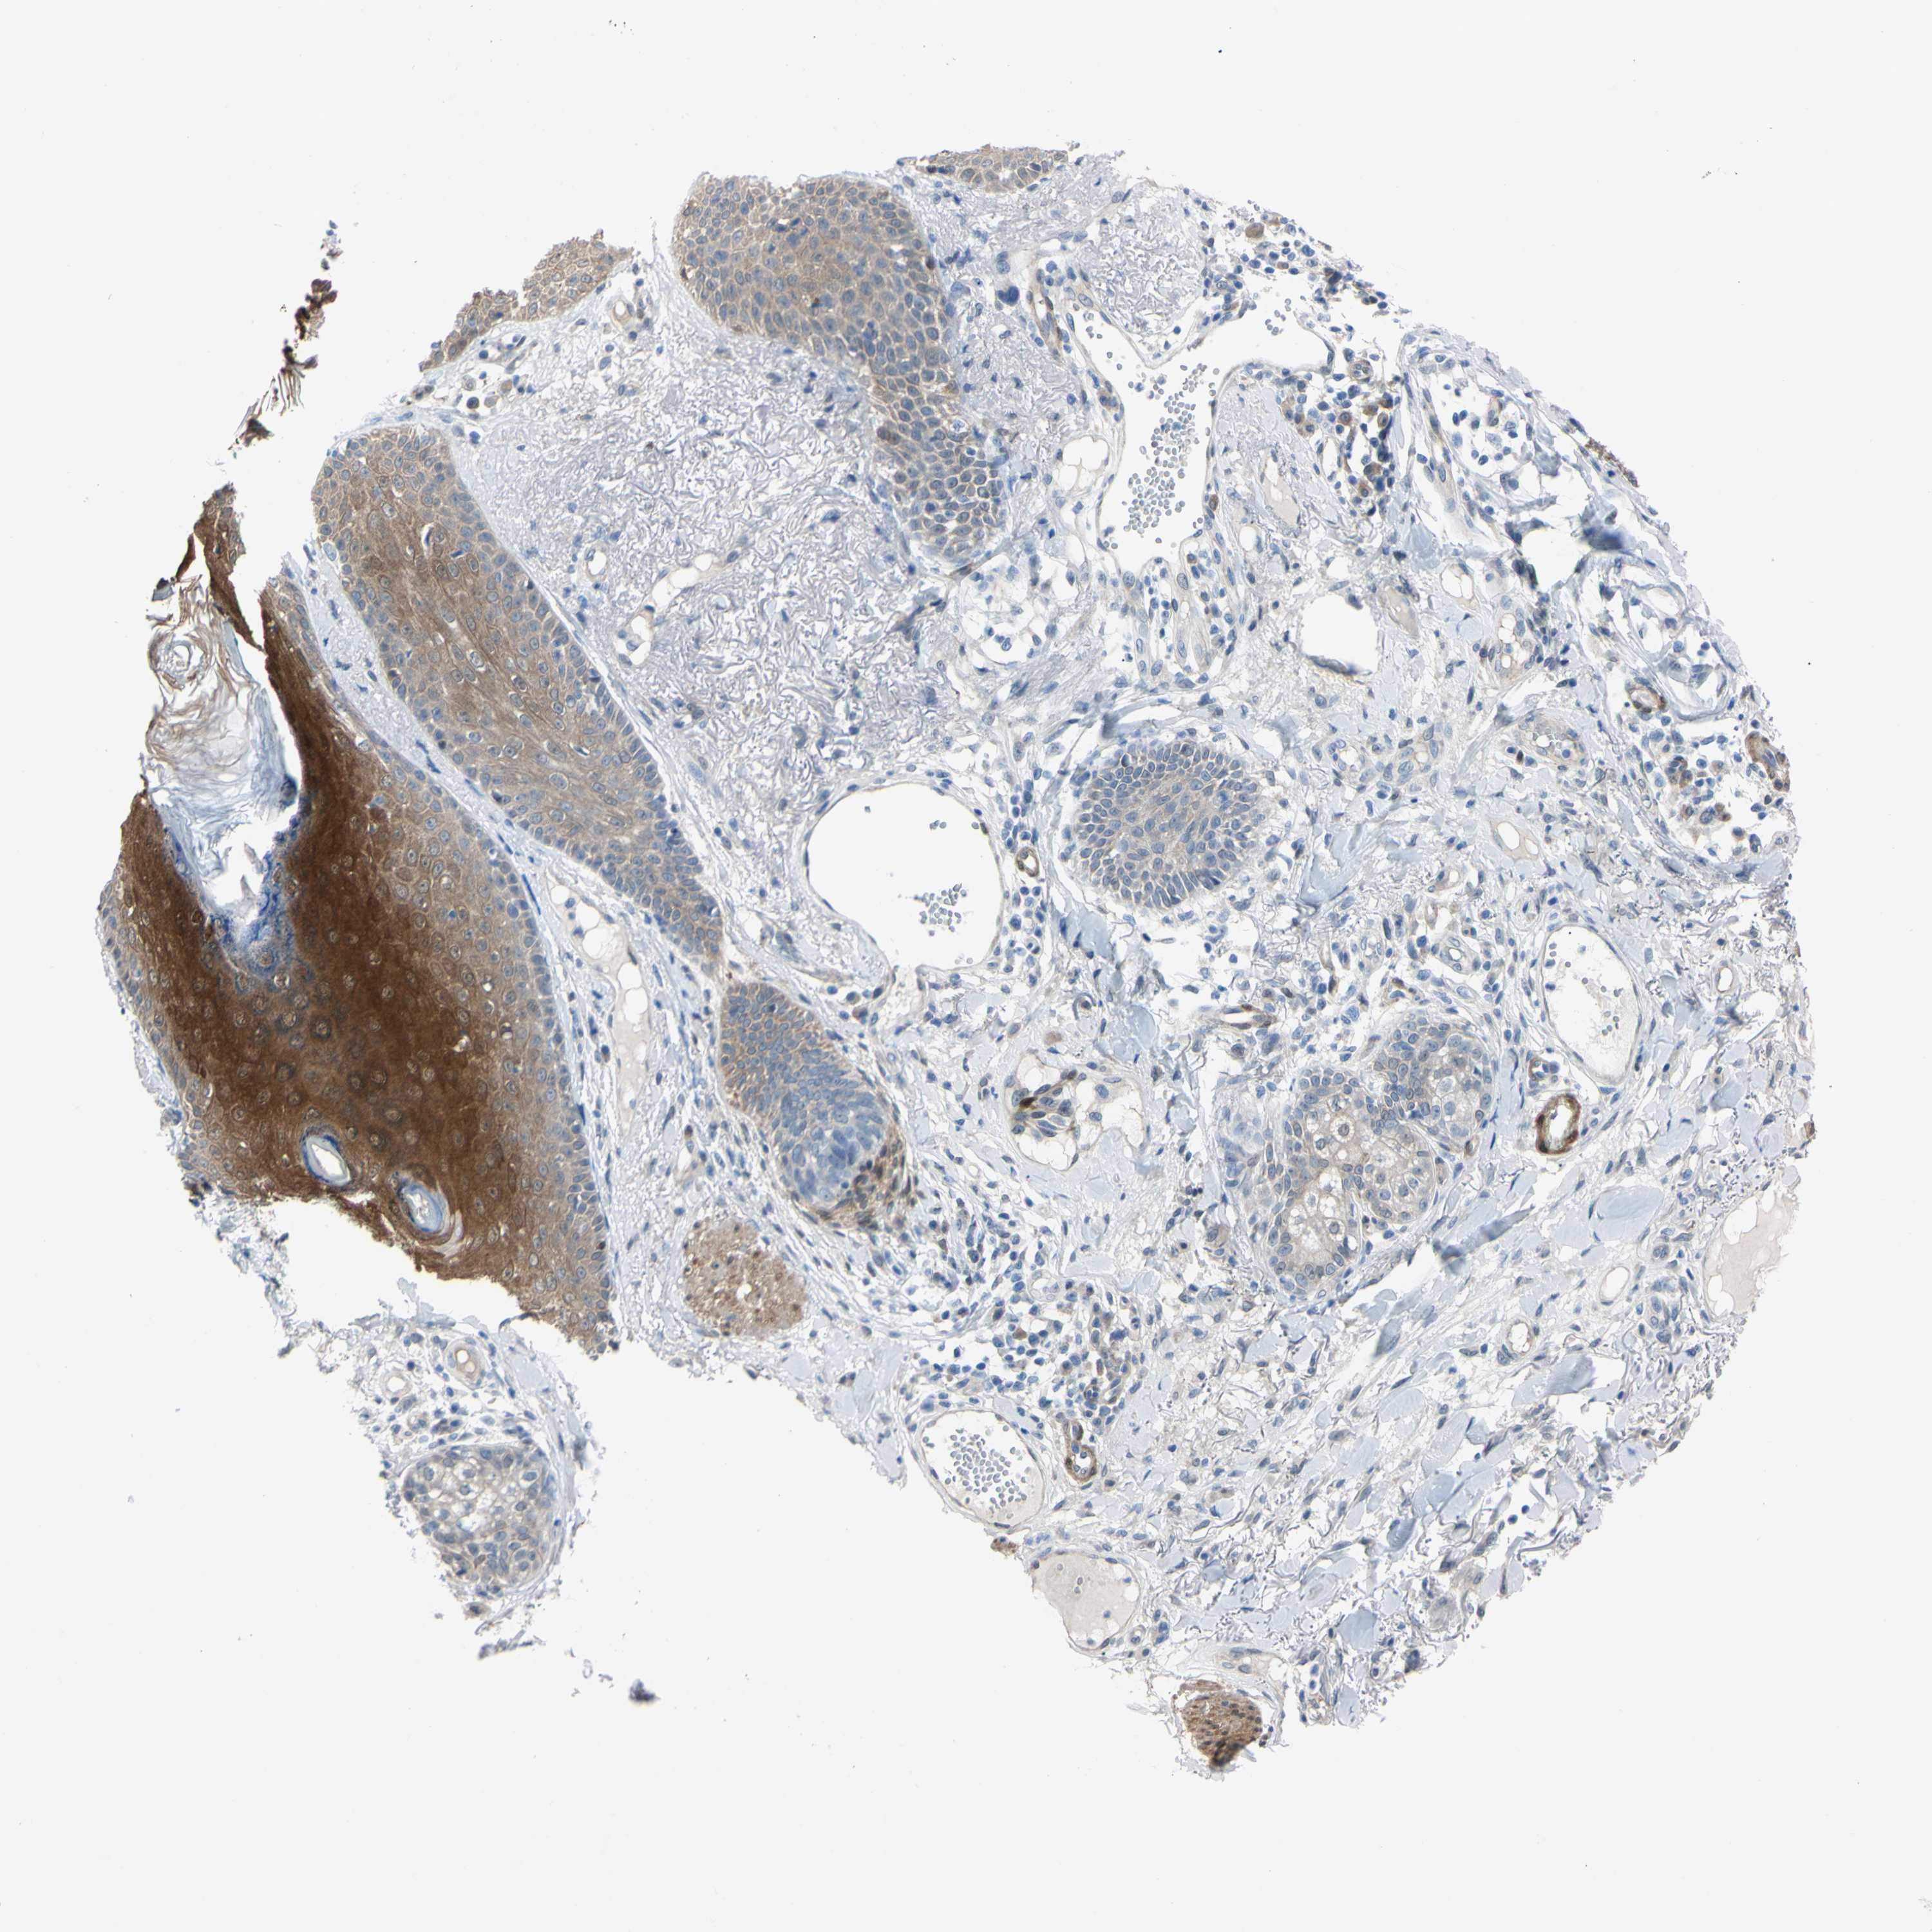

Basal cell and squamous cell cancer

SKIN CANCER - Protein expressioni

A mouse-over function shows sample information and annotation data. Click on an image to view it in a full screen mode. Samples can be filtered based on level of antibody staining by selecting one or several of the following categories: high, medium, low and not detected. The assay and annotation is described here.

Each image is clickable and will lead to virtual microscopy that enables deeper exploration of all samples and also displays staining intensity scores, fraction scores and subcellular localization as well as patient and tissue information for each sample.

Antibody CAB009208

Staining

High

Medium

Low

Not detected

Intensity

Strong

Moderate

Weak

Negative

Quantity

>75%

75%-25%

<25%

None

Location

Nuclear

Cytoplasmic/membranous

Cytoplasmic/membranous,nuclear

Squamous cell carcinoma, NOS

Basal cell carcinoma